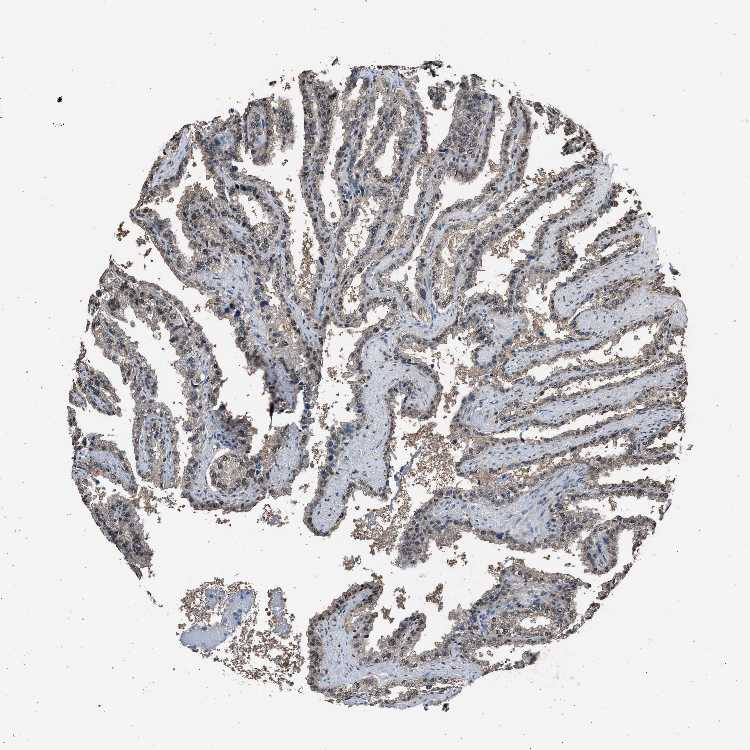

TISSUE PRIMARY DATA SEMINAL VESICLE Show tissue menu

SEMINAL VESICLE - Antibody stainingi

Antibody staining in the annotated cell types in the current human tissue is reported as not detected, low, medium, or high, based on conventional immunohistochemistry profiling in selected tissues. This score is based on the combination of the staining intensity and fraction of stained cells.

Each image is clickable and will lead to virtual microscopy that enables deeper exploration of all samples and also displays staining intensity scores, fraction scores and subcellular localization as well as patient and tissue information for each sample.

Antibody HPA018859Antibody HPA019938Antibody HPA025230Antibody CAB002679

Glandular cells MediumLowMediumHigh